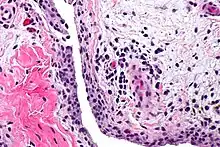

| Chronic synovitis | |

Synovitis is the medical term for inflammation of the synovial membrane. This membrane lines joints that possess cavities, known as synovial joints. The condition is usually painful, particularly when the joint is moved. The joint usually swells due to synovial fluid collection.

Synovitis may occur in association with arthritis as well as lupus, gout, and other conditions. Synovitis is more commonly found in rheumatoid arthritis than in other forms of arthritis, and can thus serve as a distinguishing factor, although it is also present in many joints affected with osteoarthritis.[1][2] In rheumatoid arthritis, the fibroblast-like synoviocytes, highly specialized mesenchymal cells found in the synovial membrane, play an active and prominent role in the synovitis.[3] Long term occurrence of synovitis can result in degeneration of the joint.